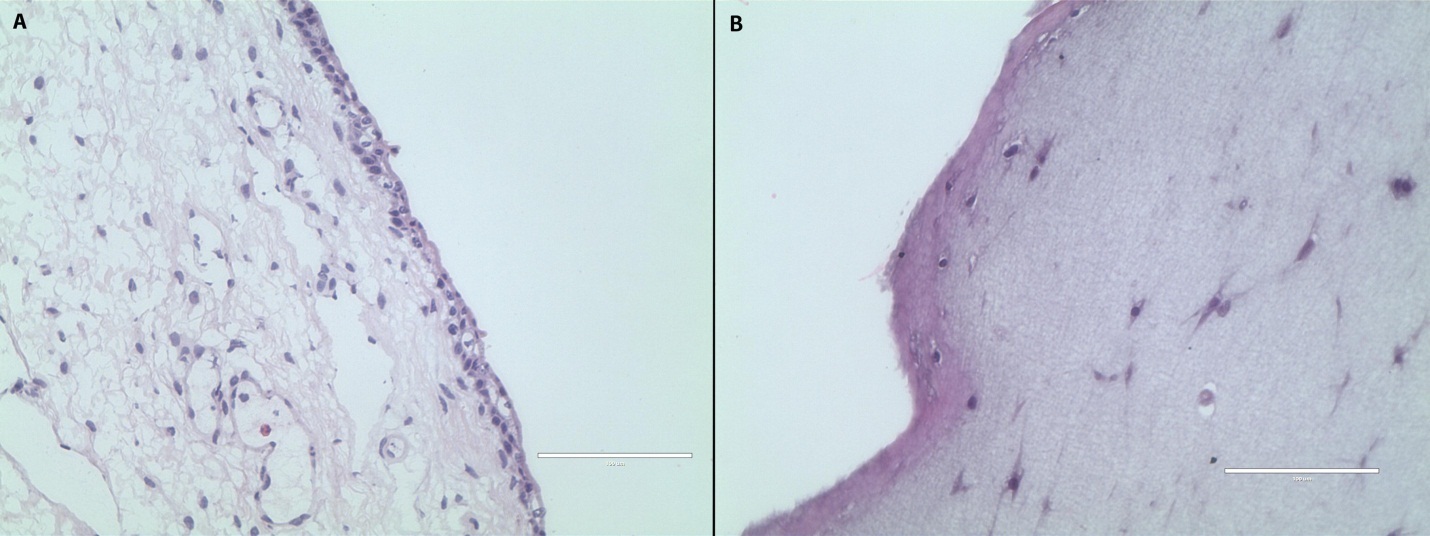

For the constructs made with rabbit fibrinogen, hematoxylin and eosin microscopy showed a fibrin lattice with similar gross morphology to the vocal fold lamina propria and epithelium. Cell nuclei were identified throughout the construct (Figure 4). There was no observable morphologic difference between constructs treated with EGF and those that were not.

Figure 4.Hematoxylin and eosin staining of rabbit true vocal fold (A) and a fibrin-rASC construct (B). The construct after 14 days of culture with EGF demonstrates a bilayered structure with cells attached throughout the construct. Magnification 40x; scale bar 100 µm.